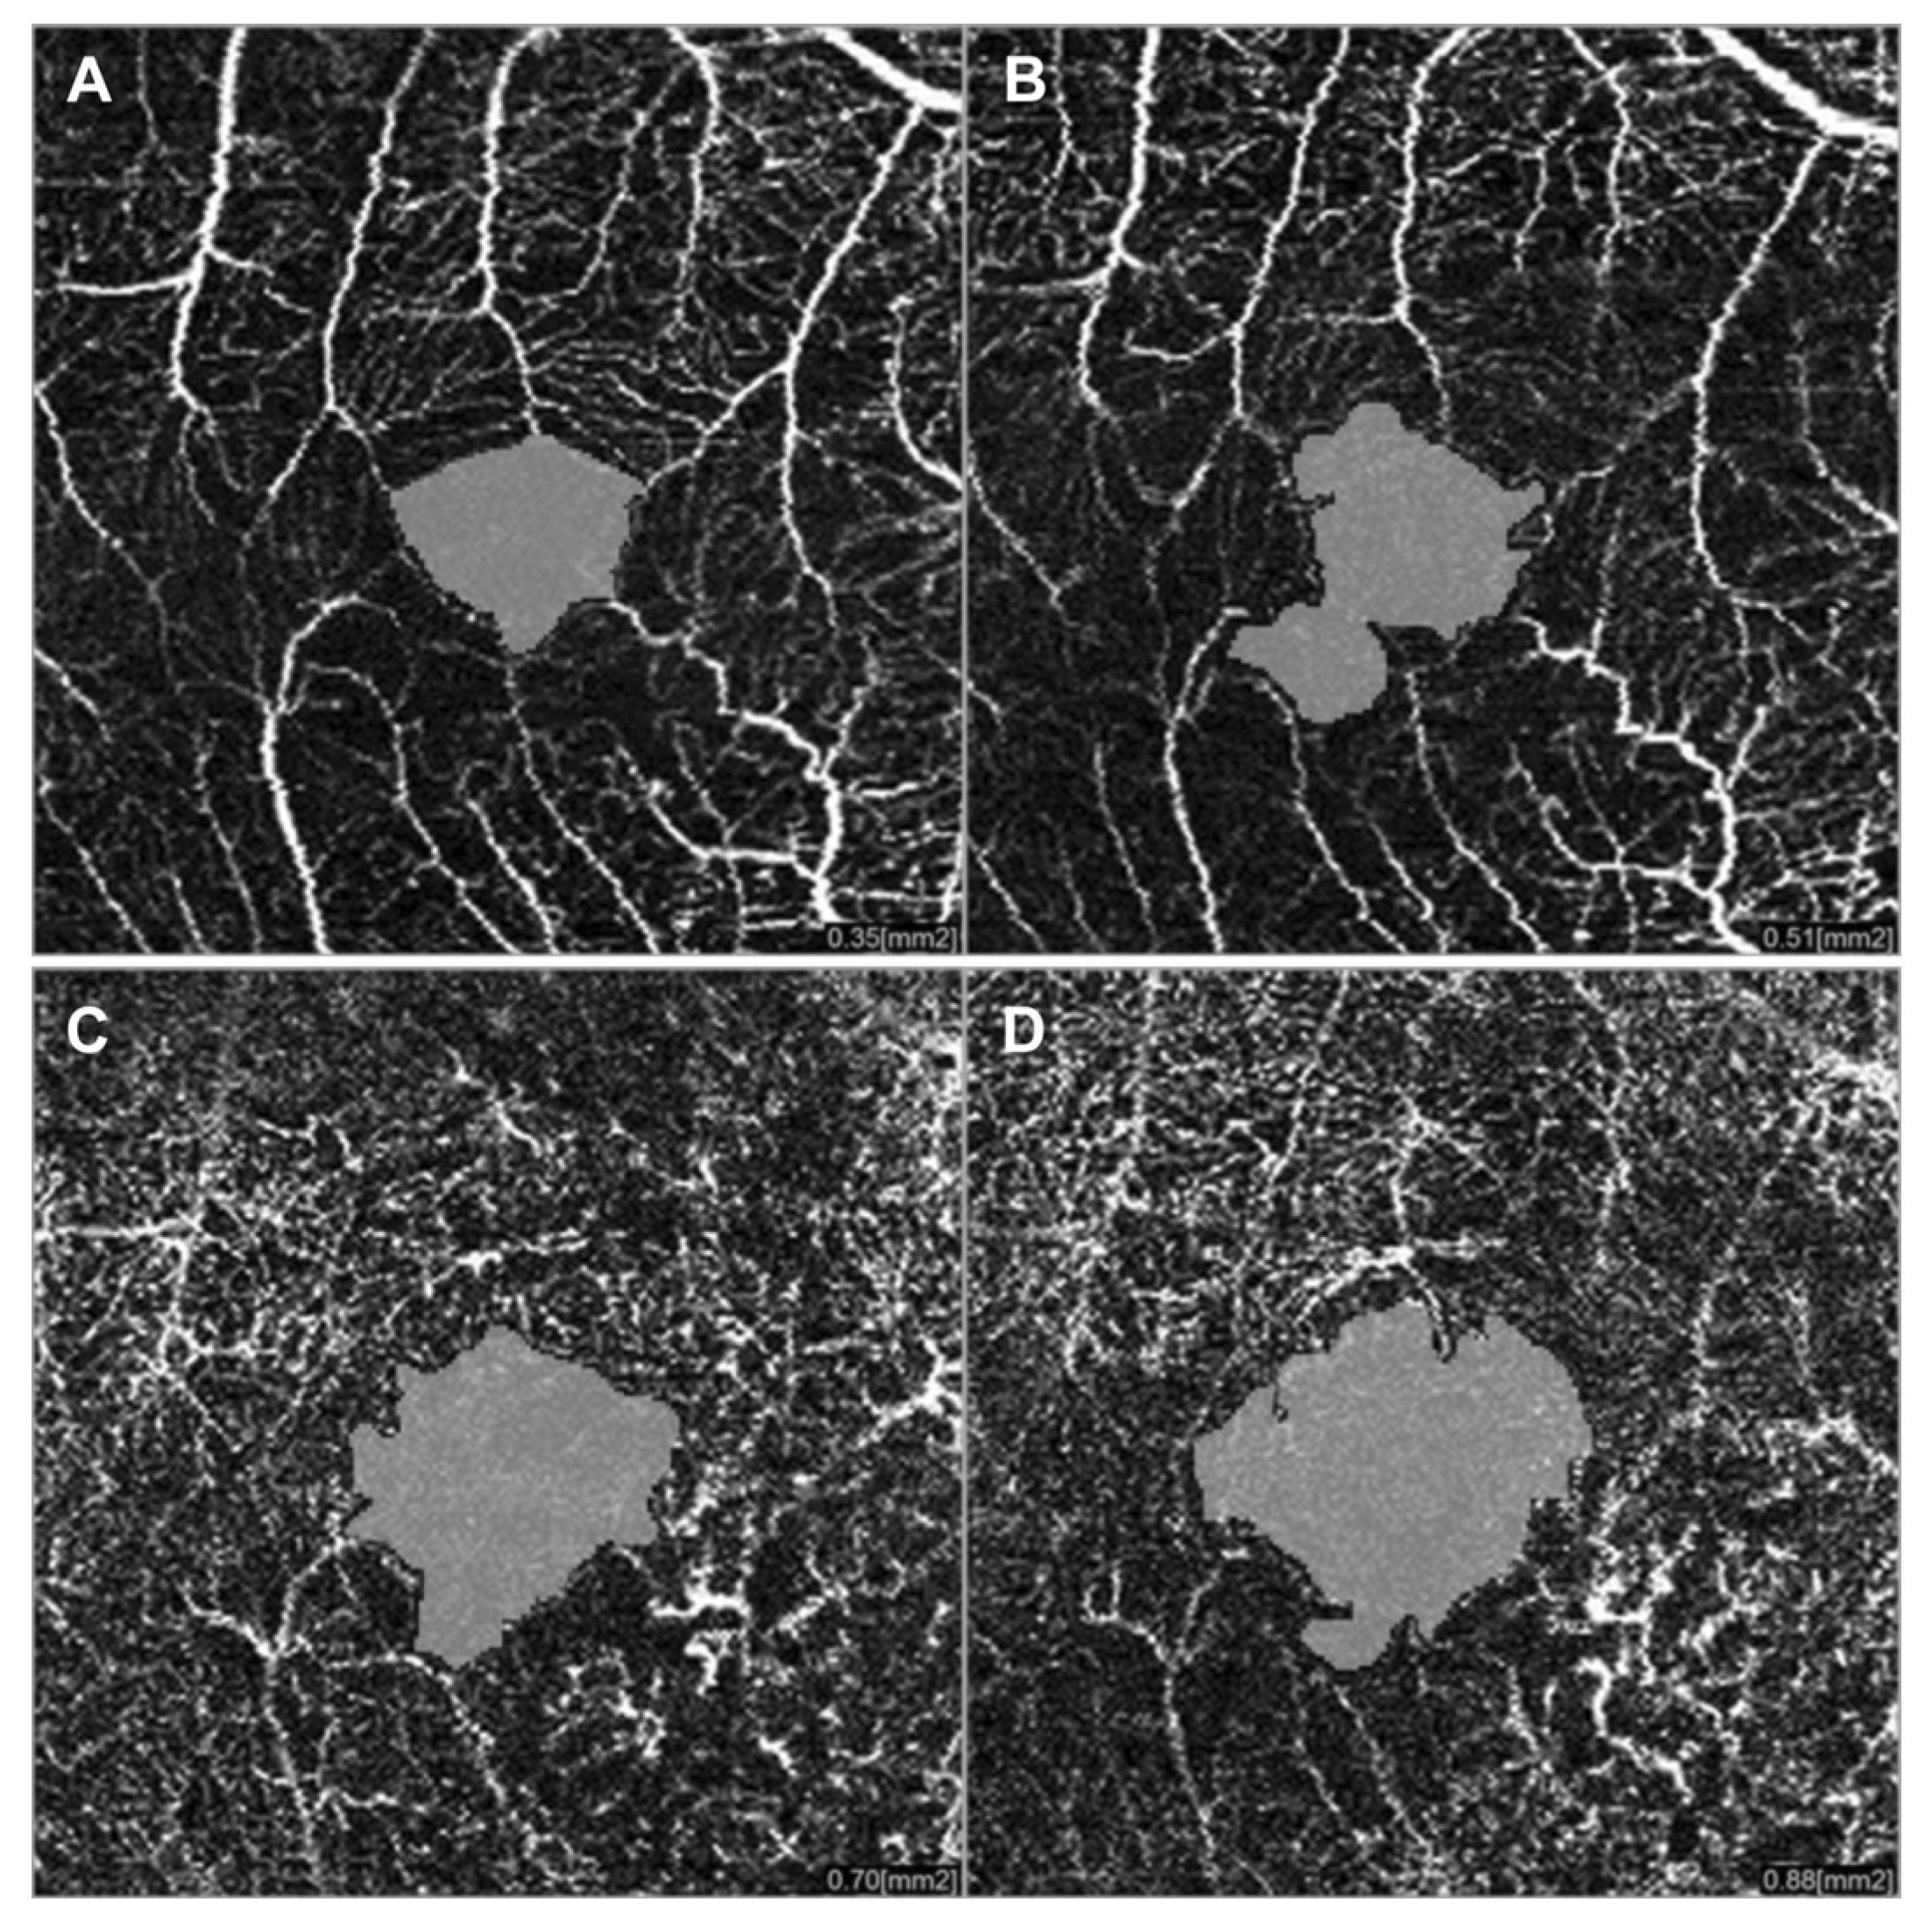

3.2. Radiation Maculopathy

- Sellam, A.; Coscas, F.; Rouic, L.L.-L.; Dendale, R.; Lupidi, M.; Coscas, G.; Desjardins, L.; Cassoux, N. Optical Coherence Tomography Angiography of Macular Features After Proton Beam Radiotherapy for Small Choroidal Melanoma. Am. J. Ophthalmol. 2017, 181, 12–19. [Google Scholar] [CrossRef] [PubMed]

- Shields, C.L.; Say, E.A.T.; Samara, W.A.; Khoo, C.T.L.; Mashayekhi, A.; Shields, J.A. Optical coherence tomography angiography of the macula after plaque radiotherapy of choroidal melanoma. Retina 2016, 36, 1493–1505. [Google Scholar] [CrossRef] [PubMed]

- Lim, L.A.S.; Camp, D.A.; Ancona-Lezama, D.; Mazloumi, M.; Patel, S.P.; McLaughlin, J.W.; Ferenczy, S.R.; Mashayekhi, A.; Shields, C.L. Wide-Field (15 × 9 mm) Swept-Source Optical Coherence Tomography Angiography Following Plaque Radiotherapy of Choroidal Melanoma: An Analysis of 105 eyes. Asia Pac. J. Ophthalmol. 2020, 9, 326–334. [Google Scholar] [CrossRef] [PubMed]

- Say, E.A.T.; Samara, W.A.; Khoo, C.T.L.; Magrath, G.N.; Sharma, P.; Ferenczy, S.; Shields, C.L. Parafoveal capillary density after plaque radiotherapy for choroidal melanoma. Retina 2016, 36, 1670–1678. [Google Scholar] [CrossRef]

- Parrozzani, R.; Midena, E.; Trainiti, S.; Londei, D.; Miglionico, G.; Annunziata, T.; Frisina, R.; Pilotto, E.; Frizziero, L. Identification and classification of macular morphologic biomarkers related to visual acuity in radiation maculopathy. Retina 2020, 40, 1419–1428. [Google Scholar] [CrossRef]

- Matet, A.; Daruich, A.; Zografos, L. Radiation Maculopathy After Proton Beam Therapy for Uveal Melanoma: Optical Coherence Tomography Angiography Alterations Influencing Visual Acuity. Investig. Opthalmol. Vis. Sci. 2017, 58, 3851–3861. [Google Scholar] [CrossRef]

- Daruich, A.; Matet, A.; Schalenbourg, A.; Zografos, L. Intravitreal anti–vascular endothelial growth factor treatment at 2-month intervals reduces foveal avascular zone enlargement and vision loss in radiation maculopathy. Retina 2019, 39, 1519–1526. [Google Scholar] [CrossRef]

- Cennamo, G.; Montorio, D.; Bernardo, R.; Farella, A.; Liuzzi, R.; Breve, M.A.; Reibaldi, M.; Cennamo, G. Retinal Vascular Changes in Radiation Maculopathy after Intravitreal Ranibizumab by Optical Coherence Tomography Angiography. J. Clin. Med. 2020, 9, 1618. [Google Scholar] [CrossRef]

- Li, Y.; Say, E.A.T.; Ferenczy, S.; Agni, M.; Shields, C.L. Altered parafoveal microvasculature in treatment-naive choroidal melanoma eyes detected by optical coherence tomography angiography. Retin 2017, 37, 32–40. [Google Scholar] [CrossRef]